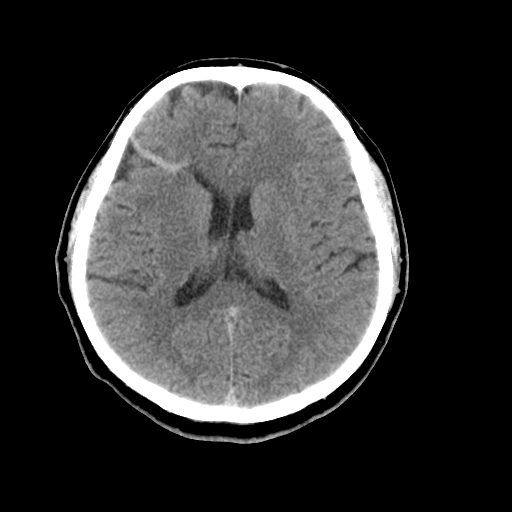

以下是引用liuyue在2008-4-28 13:34:00的发言:[br]右额叶条状高密度影,边缘清楚,周围未见水肿及占位.[br]考虑:血管畸形可能性大.[br]建议:强化ct扫描或mri检查.除外脑回钙化.

以下是引用论黑辩白在2008-4-28 12:53:00的发言:[br]右额叶局限性脑萎缩,右额叶见条状高密度影,建议mri进一步检查。[br][br][本贴已被 论黑辩白 于 2008-4-28 13:08:16 修改过]